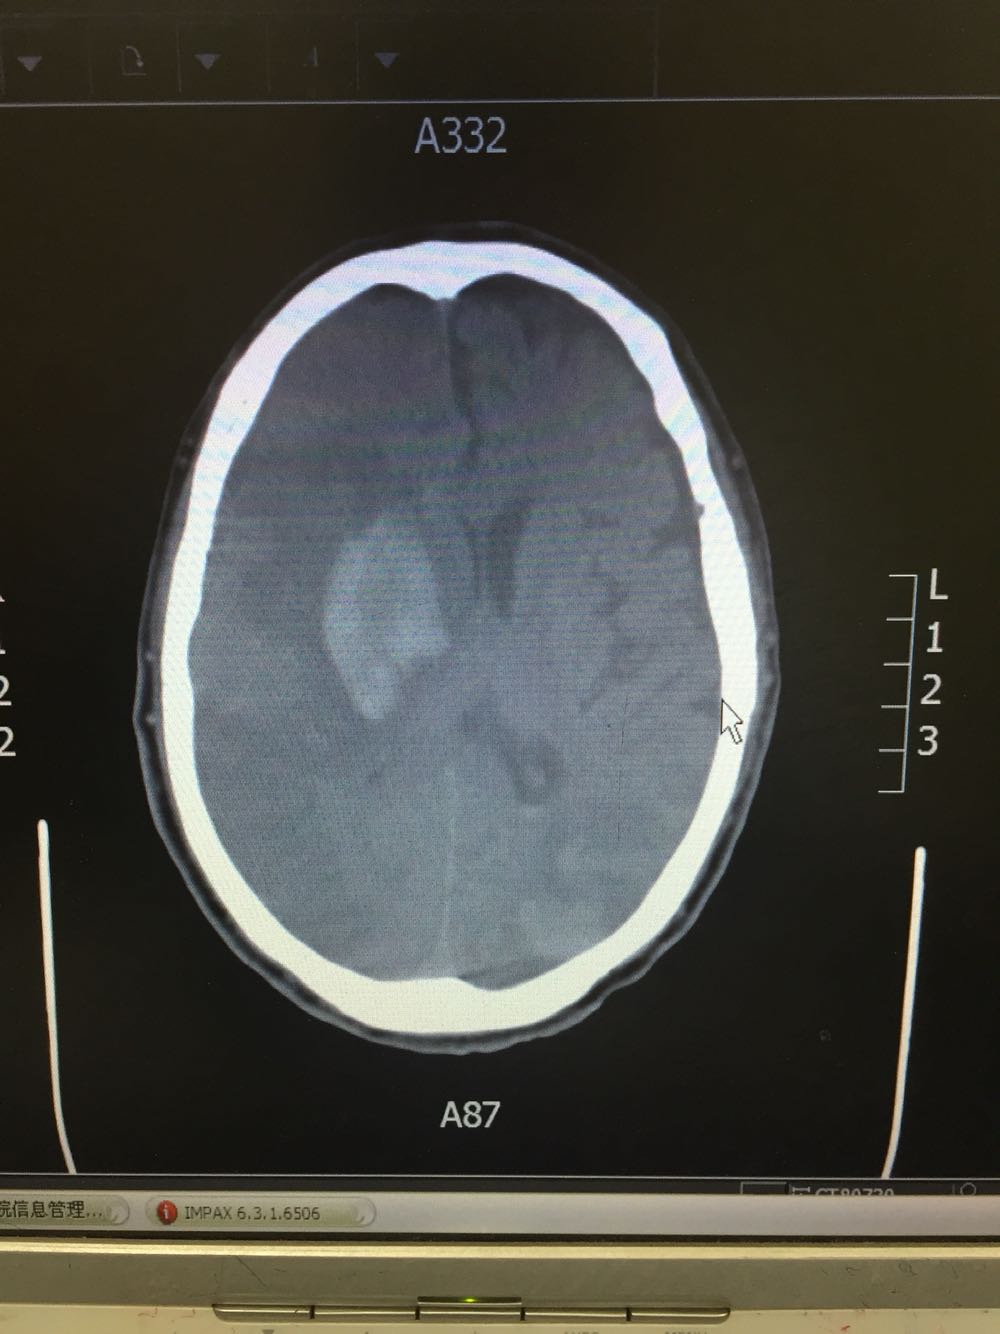

患者入院治疗后症状一度好转,左侧肢体肌力3级+,于入院后第二日病情突然加重,伴意识障碍,头DWI示:脑梗死伴脑出血 右侧大脑中动脉闭塞。停止当前治疗方案,脱水脑保护,营养神经对症治疗。入院后第5日复查头CT示:右侧大面积脑梗死,脑出血吸收期,伴左侧枕叶脑出血。患者左侧枕叶脑出血不好解释,能否是搬运及护理时外伤所致?